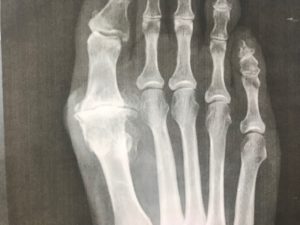

Il complétera l’examen par la pratique de radiographies et de scanner des deux pieds de face et profil, en charge, et si nécessaire une I.R.M.

Sur les radiographies on observe une disparition de l’espace cartilagineux: les os se touchent directement, et la présence de « becs de perroquet » (ostéophytes).

A un stade plus avancé, on observe une densification de l’os en regard de l’articulation, et des trous osseux (géodes, os comme du « gruyère »).